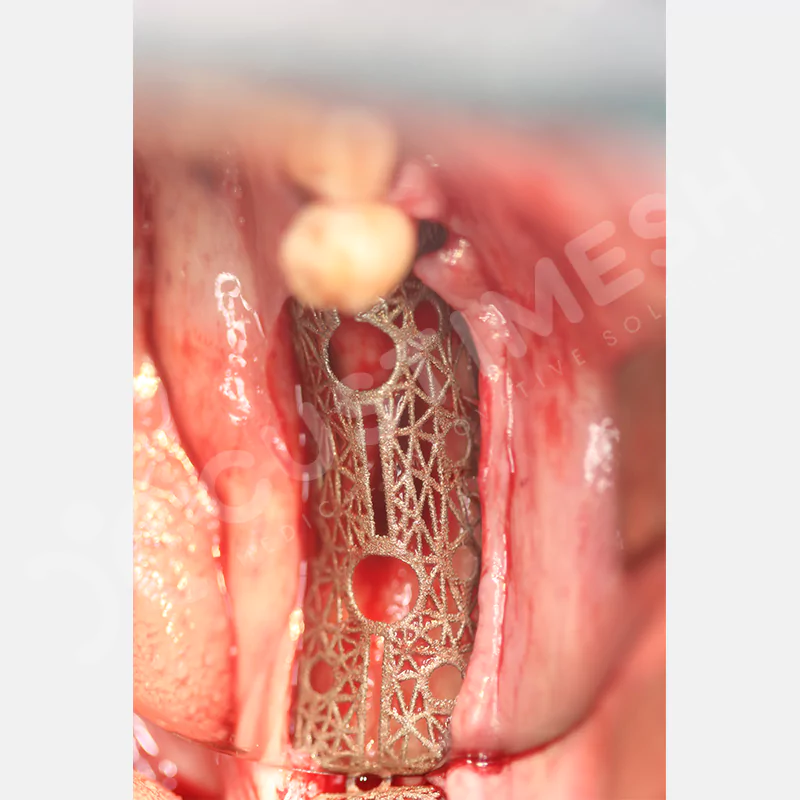

Medikal sınıf titanyumdan, hastanın bilgisayarlı tomografi verileri kullanılarak CAD yazılımlarıyla tasarlanan ve 3D baskı teknolojisiyle üretilen bu yenilikçi çözüm, özellikle kompleks kemik defektlerinde standart meshlerin sağlayamadığı üstün mekanik stabilite ve mükemmel adaptasyon özellikleri sunar. Anatomik yapıya tam uyum sağlayarak greft materyalinin yerinde kalmasını garanti ederken, optimal vaskülerizasyonu destekleyerek kemik rejenerasyon sürecini hızlandırır.

VAKA 1

VAKA 2

VAKA 3